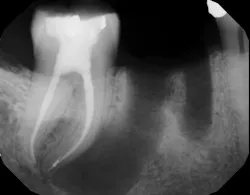

- The type of endodontic treatment dictates the length of healing. Nonsurgical endodontic treatment has a usual healing time of three months. Surgical intervention such as an apicoectomy due to large lesion size can take six to 12 months to heal (figures 1 and 2).